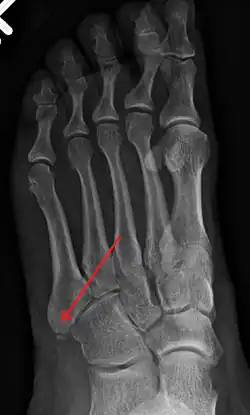

The metatarsal bones are often broken by association football (soccer) players. These and other recent cases have been attributed to the lightweight design of modern football boots, which provide less protection to the foot. In 2010 some football players began testing a new sock that incorporated a rubber silicone pad over the foot to provide protection to the top of the foot.[8] Stress fractures are thought to account for 16% of injuries related to sports participation, and the metatarsals are the bones most often involved. These fractures are sometimes called march fractures, based on their traditional association with military recruits after long marches. The second and third metatarsals are fixed while walking, thus these metatarsals are common sites of injury. The fifth metatarsal may be fractured if the foot is oversupinated during locomotion.[9]

X-ray of foot. -